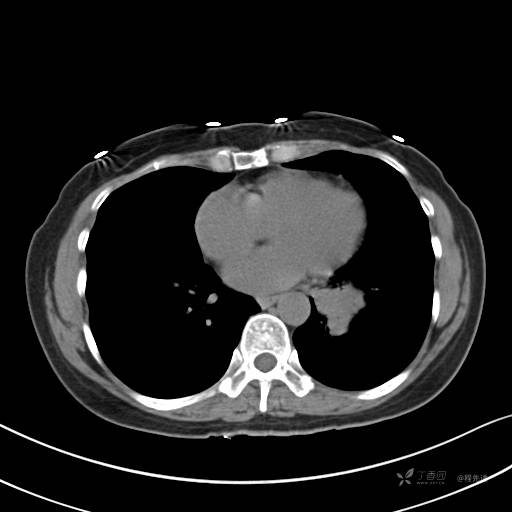

增强动脉期

动脉期CT值约74HU